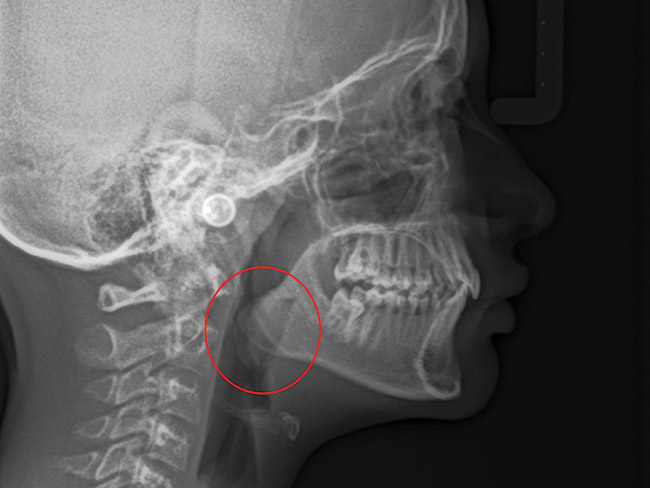

(15.) Cephalometric evaluation demonstrates significant tonsillar blockage of the airway and bimaxillary retursion.

Figure 15

The point of obstruction tends to determine the type of skeletal impact. Nasal obstruction from enlarged turbinates, blocked ostium maxillare, deviated septum, or nasal valve stenosis creates Angle occlusions of Class I, II, and III equally (Figure 8). The maxilla in these cases is positioned posteriorly and the mandible is posterior-inferior. The facial type is most commonly dolicocephalic. Blockage of the airway predominately by the adenoids will create growth patterns that yield mostly Class II occlusions and anterior open bite with both jaws located posterior-inferiorly. Facial type is again dolicocephalic with the typical long-thin “adenoidal” face49 (Figure 9 through Figure 12). If the tonsillar tissue is responsible for the airway obstruction, the tongue will have an abnormal resting posture. Class III occlusions will be more common with the maxilla normal or posterior placed (Figure 13 through 15). The tongue may direct the mandible anteriorly or, because the tongue is not in the roof of the mouth driving A point anterior, the maxilla will become bimaxillary retrusive.50 In some cases, the anterior posture of the tongue will create an open bite. This is incorrectly referred to as a tongue thrust. The impact from a thrust does not alter the tooth position. Long-term, low forces cause tooth movement. The posture of the tongue against or between the anterior teeth due to the excessive tonsillar size creates the open bite (Figure 16 and Figure 17). Facial types in this group are more brachyfacial. Lastly, if the airway is blocked through a combination of factors, the Angle classification will be either Class II or III. The maxilla will be in a normal location and the mandible will be the affected arch (Figure 18). These craniofacial changes are not restricted to OSA; all SDB will create unique alterations depending on the patient compensation. Children with UARS have been reported to display high, narrow palates, dolicofacial form, and a Class II malocclusion, indicative of largely adenoidal blockage.51

Tonsils and adenoids should be judged against the relative size of the airway rather than the absolute size of the lymphoid tissue46 (Figure 5 and Figure 6). Adenoids are located at the posterior of the nasal cavity on the roof of the nasopharynx (Figure 7). The normal distance from the adenoids to the soft palate for an acceptable airway should be at least 12 mm. For each millimeter decrease, the odds of the child snoring increase 1.61 times. Mouth breathers typically show a smaller upper airway dimension as well.47 The adenoid and tonsillar obstruction creates the trigger, but the deviate facial and neck muscle recruitment and tongue hypotonia cause the maldevelopment.48